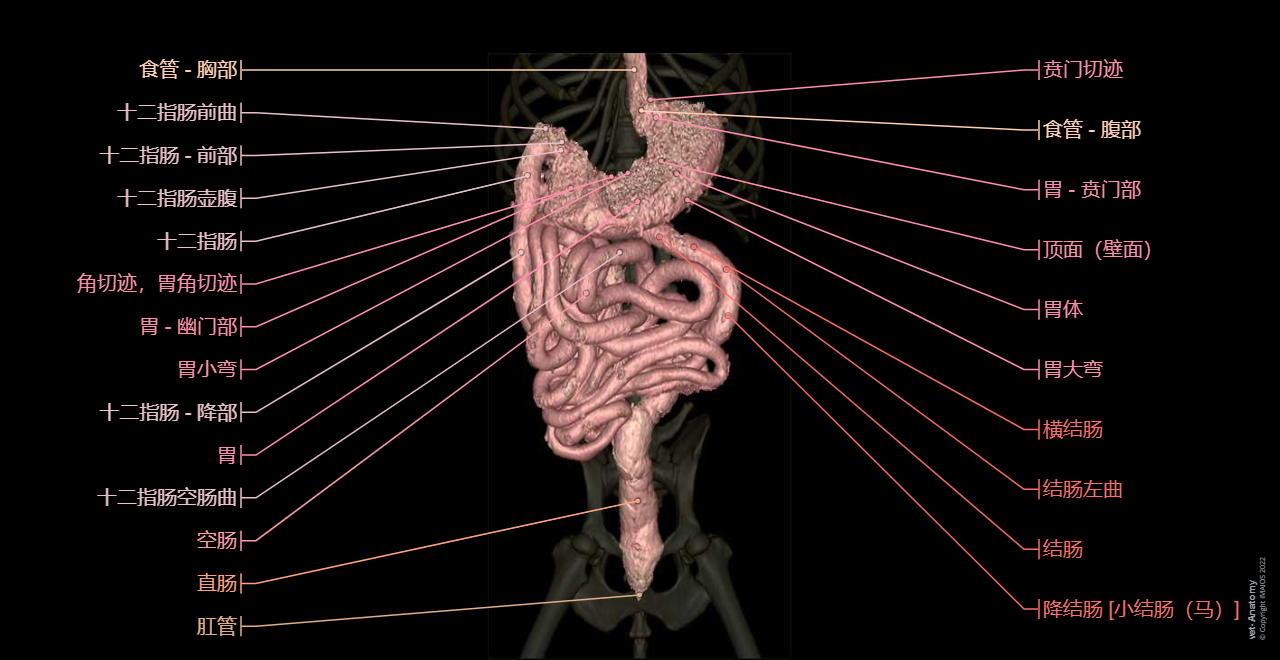

在vet-Anatomy动物图集的此模块中,计算机断层扫描(CT)显示了标有解剖结构的犬科腹腔和骨盆横截面,并用3D图像显示犬科腹部。

CT图像存在3个平面方向(横向,矢状和背侧),并且使用两种对照方式(软组织/血管和骨骼)展现。本模块的末尾提供其他3D解剖图像,便于进一步了解犬科总体解剖结构,展示了骨骼、内脏(肝脏、脾脏、胰腺、消化道)、泌尿生殖系统、动脉、全身静脉系统(主要是尾腔静脉及其分支)、门静脉系统、肌肉和表面解剖的三维容积透视图。

Dog - Digestive system - 3D - Anatomy: Stomach, Duodenum, Jejunum, Ileum, Small intestine, Large intestine, Colon, Rectum